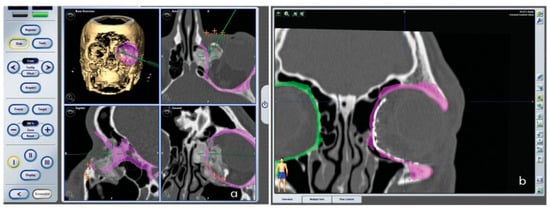

• Reconstruction using titanium meshes (Figure 3).

By performing the surgical navigation directly on the 3D model, we were able to evaluate the reconstruction position and confirm the match between mirroring and the positions of the meshes. Then the position of the screws and the orientation of the titanium meshes used in the reconstruction were imported into the navigation software. After completion of the planning phase, the patient underwent surgical resection and reconstruction procedures.

Finally, for confirmation and accuracy purposes, the correct position of the meshes was further evaluated through navigation. The aim was to reproduce the resection and reconstruction designed during preoperative planning (Figure 8a).

Immediately after surgery, a CT scan of the surgical site was obtained to verify the correct positioning of the reconstructive meshes. Based on the superimposed pre- and postoperative images, the virtual orbital profile obtained with mirroring perfectly matched that achieved with reconstruction (Figure 8b). There were no complications in early postoperative phase. Complete resolution of edema was in approximately 10 days. We medicated the patient daily, washing the eye with saline solution. Hospitalization lasted 3 days.

Figure 3. Rapid prototyping model without neoplasia, definition of the area to be reconstructed and preoperative virtual navigation after reconstruction.

Figure 8. (a) Real-time navigation imaging; (b) postoperative CT scan superimposition on preoperative planning.